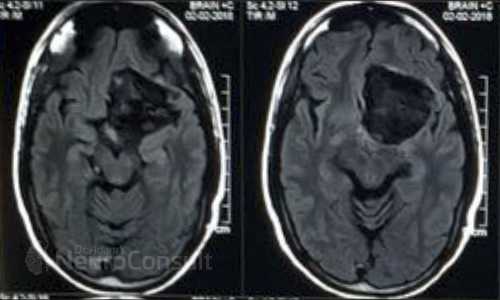

I am an consultant neurosurgeon. I have completed my Masters in General Surgery from SN Medical College, Agra and thereafter completed my formal Neurosurgical training from one of India's premier institute ie. SREE CHITRA TIRUNAL INSTITUTE OF SCIENCES AND TECHNOLOGY, Trivandrum (An institute of national importance). I have special interest in brain and spinal tumors.

I've been involved in numerous treatment of brain and spine-related ailments like spinal joint and disc disease, brain infarction(stroke/paralysis), hydrocephalus etc. to name the few. I am passionate about patient care and strives very hard for their recovery both physically and mentally.